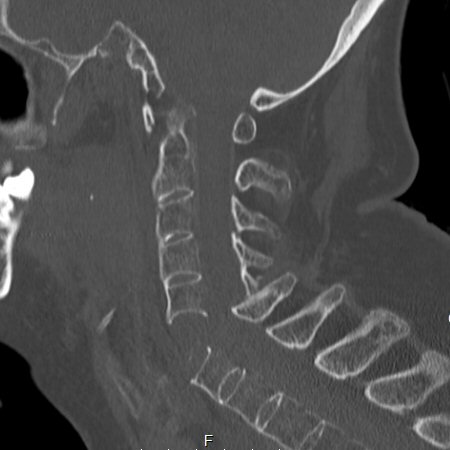

Notera att vid Bechterews sjukdom eller DISH-förändringar så blir frakturer ofta instabila. MR-undersökning krävs ofta inför operationsbeslut.

Fraktur i DISH-rygg mellan C2-C3 och C3-C4. Tetraplegisk.